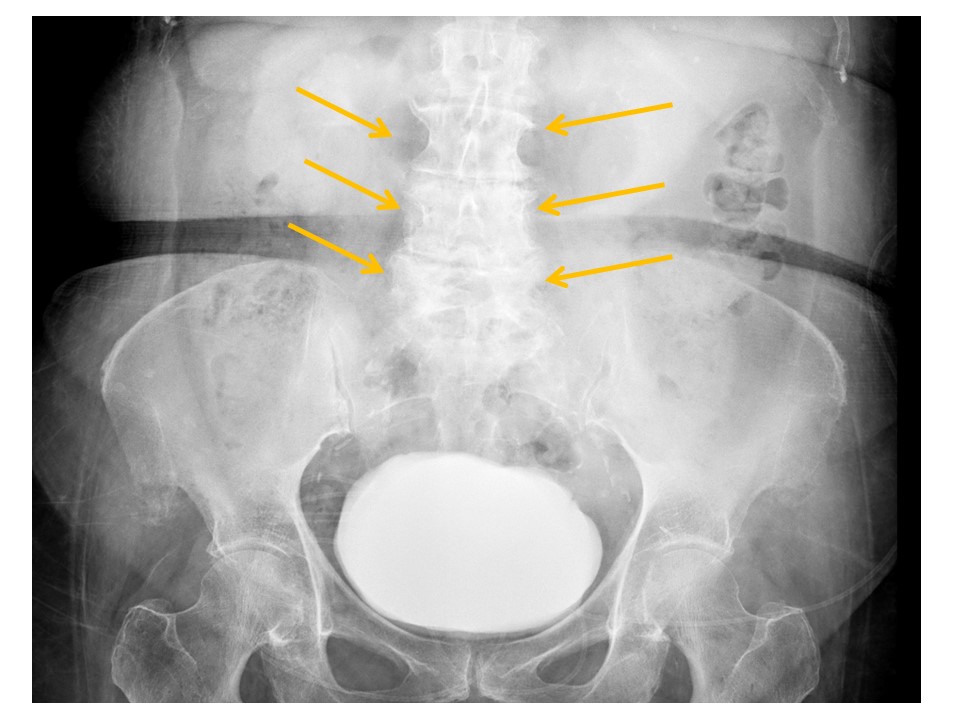

VISUALIZED LUMBAR SPINE

There are compression fractures. [Yes/No]

There are transverse process fractures. [Yes/No]

There is lumbar spine degeneration. [Yes/No]